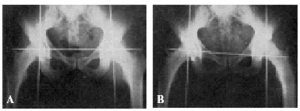

Al aplicar dicha técnica en el vivo, hay que tener sumo cuidado de que la línea que pasa por ambas espinas ilíacas anterosuperiores se mantenga perpendicular a la línea xifoidea púbica (véase la fig. 14).

Figura 14. A: radiografía obtenida sin exploración radioscópica previa. Obsérvese cómo el alambre de Kirschner que pasa inmediatamente por encima de la espina del pubis, corresponde, en ambos lados, exactamente a la fosita de inserción del ligamento redondo. El fémur, en ambos lados, está colocado en la misma posición que en el acto operatorio. B: si se bascula la pelvis, y por lo tanto, la línea que pasa por ambas espinas ilíacas anterosuperiores deja de ser perpendicular a la línea xifoidopúbica, deja de tener valor el punto de referencia que preconizamos.